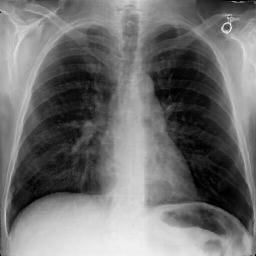

Refer to caption

Train

Valid

(a)XR(a)X_{R}

Test

(b)X^R(b)\hat{X}_{R}

(c)XA:ut(c)X_{A}:\mathcal{L}_{ut}

id\mathcal{L}_{id}

ut+id\mathcal{L}_{ut}+\mathcal{L}_{id}

Fig. 3: Anonymization results. Real images XRX_{R} randomly selected from the training, validation, and test sets are displayed in the first column. The corresponding reconstructed images X^R\hat{X}_{R} are displayed in the second column. The anonymized images XAX_{A} are displayed in the last three columns.

Qualitative Results The visualization results are shown in Fig. 3. In this figure, the anonymized images optimized using only the utility loss ut\mathcal{L}_{ut} (column 3) exhibit greater visual similarity to their real counterparts (column 1), while those optimized using only the identity loss id\mathcal{L}_{id} (column 4) appear more distinct from their originals. Additionally, the anonymized images optimized with both the ut\mathcal{L}_{ut} and the id\mathcal{L}_{id} (column 5) strike a balance, appearing more realistic by simultaneously considering both identity removal and utility preservation.